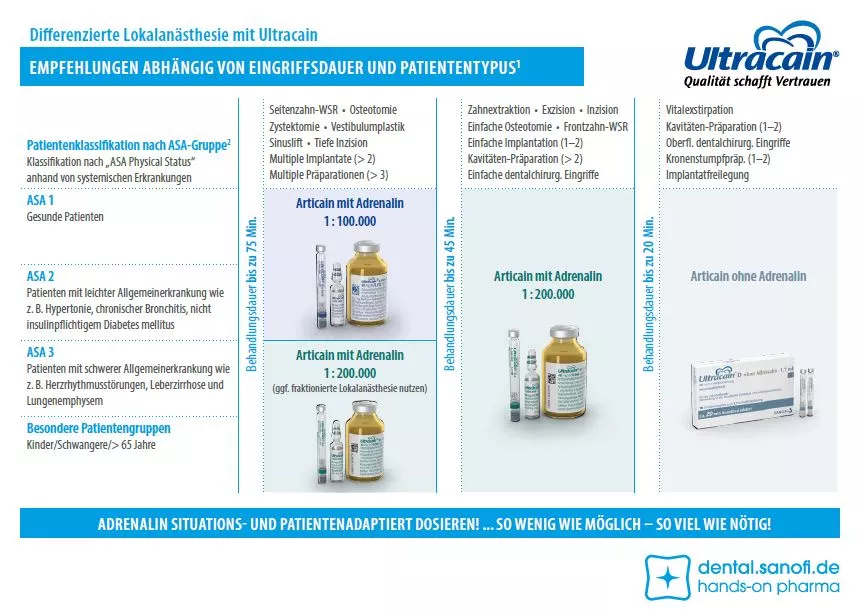

Risikogruppen für die Lokalanästhesie sind nicht nur Patienten mit Vorerkrankungen, wie Herz- Kreislauferkrankungen, Leberinsuffizienz oder endokrinologischen Erkrankungen. Auch die verschiedensten Patientengruppen, z. B. der unterschiedlichen Altersklassen oder Schwangere, spielen eine wichtige Rolle. Auf der Karte sind die Patienten nach ASA-Gruppe und besonderen Patienten klassifiziert (siehe Tabelle 1). Patienten ab einer Einstufung von ASA 4 gelten als nicht ausreichend belastbar und sollten daher nur stationär behandelt werden [7].

Nach Indikation und Eingriffsdauer ergeben sich daraus folgende Empfehlungen für die Patientengruppen [8]:

- Längere, schmerzhafte Eingriffe mit einer Behandlungsdauer bis zu 75 Minuten (z. B. Wurzelspitzenresektion im Seitenzahnbereich, Osteotomie, Setzen von mehr als zwei Implantaten, Vestibulumplastik, Sinuslift, multiple Präparationen): Bis ASA 2 kann Articain mit dem Adrenalinzusatz 1:100.000 verwendet werden (Ultracain® D-S forte) [9], ab ASA 3 und besonderen Patienten sollte dieser reduziert werden und ggf. eine fraktionierte Anästhesie erfolgen.

- Routineeingriffe mit einer Behandlungsdauer von bis zu 45 Minuten (z. B. Zahnextraktion, Exzision, Inzision, Kavitäten-Präparationen, einfache Osteotomien, Implantationen und chirurgische Eingriffe): Über alle Patientengruppen hinweg kann Articain mit einem reduzierten Adrenalinzusatz von 1:200.000 verwendet werden (Ultracain® D-S), vorausgesetzt es liegen keine Kontraindikationen vor [9].

- Bei kurzen, weniger schmerzhaften Eingriffen mit einer Behandlungsdauer von bis zu 20 Minuten (z. B. <2 Kavitäten-Präparationen, oberflächliche chirurgische Eingriffe, Kronenstumpfpräparationen, Implantatfreilegung, Vitalexstirpation): Alle Patienten können Articain ohne Adrenalin erhalten (Ultracain® D ohne Adrenalin), vorausgesetzt es liegen keine Kontraindikationen vor [10].